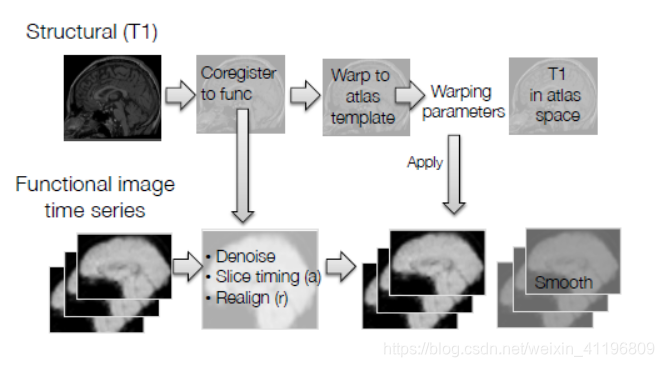

图1为fMRI数据预处理流程

在这个模块中我们会讨论将图像与脑图谱模板(atlas template)配准及平滑(smoothing)的过程。通常来说,每个人的大脑都是不同的,两个个体的大脑尺寸差异可以达到30%,大脑形状也可能存在显著差别,所以标准化(normalization)所做的正是通过拉伸、压缩以及卷绕使得扫描得到的大脑与标准大脑模板一致。这对于组分析(group analysis)而言很重要,因为我们想要对比不同的大脑,当我们关注某一个体素(voxel)时,我们希望能够在所有被试个体的扫描图像中看到这个体素,这就需要所有的大脑“匹配”至同一个标准脑空间(standard brain space)。所以高分辨率的T1结构像现在又被配准至标准空间(normalized space),如下图2所示。

图2将高分辨率T1结构像配准至标准空间

注:从图 1的流程图中可以看出,课程中所讲的标准化是先将高分辨率的T1结构像与标准模板(此处的标准模板是高分辨率的结构像标准模板)进行配准,再直接将这些配准参数应用于功能像上(因为功能像之前已经与结构像进行过一次配准),这也是目前比较普遍的一种做法,因为T1结构像分辨率高,大脑内部结构可精准对齐。但还有另外一种做法,可以直接将功能像与标准模板(此处的标准模板是低分辨率的功能像标准模板)进行配准,这种做法在SPM软件中比较常见,不需要借助T1结构像,但在对齐效果上较差。

最后,再来回顾一下fMRI数据预处理的流程(如下图 5所示),扫描得到的结构像和功能像都需要进行预处理。结构像,通常是T1加权,需要与功能像进行配准,并配准至标准空间。功能像,通常是T2*加权,需要进行去噪,扫描层时间校正,以及头动校正之后,将标准化过程中结构像的配准参数应用于功能像上,使功能像也配准至标准空间(如MNI脑图谱)。最后,功能像进行平滑,就可以开始数据分析了。

图 5 fMRI数据预处理流